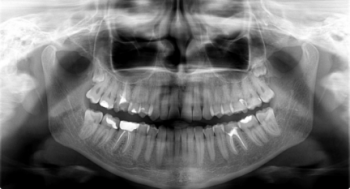

Oferujemy wysokiej jakości badania diagnostyczne, takie jak: RTG punktowe, pantomogram, cefalometria, tomografia CBCT, cyfrowy skan zębów oraz dentystyczny protokół fotograficzny.

Efektywne leczenie stomatologiczne w większości przypadków wymaga dokładnej diagnostyki, opierającej się na zobrazowaniu stanu uzębienia, kości szczęki czy żuchwy. Jednym z popularnych sposobów diagnostyki stomatologicznej jest zdjęcie pantomograficzne, czyli pantomogram. Pozwala ono uzyskać precyzyjny obraz struktur, z odwzorowaniem wszelkich krzywizn i ewentualnych nieprawidłowości. Zaawansowaną diagnostykę zapewnia tomografia komputerowa CBCT, która oferuje obrazowanie w technologii 3D.